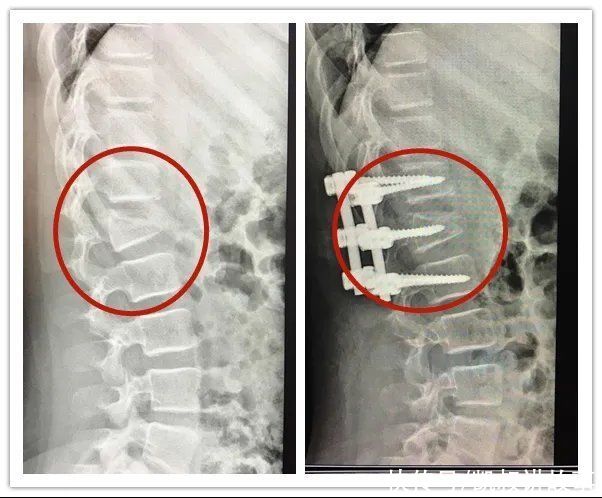

经CT检查显示,萱萱第一腰椎椎体爆裂性骨折,且存在明显的后凸畸形。好在手术很顺利,但萱萱需要躺着静养好一段时间,如果要下地行走,需要佩戴好保护支具。

萱萱手术前后